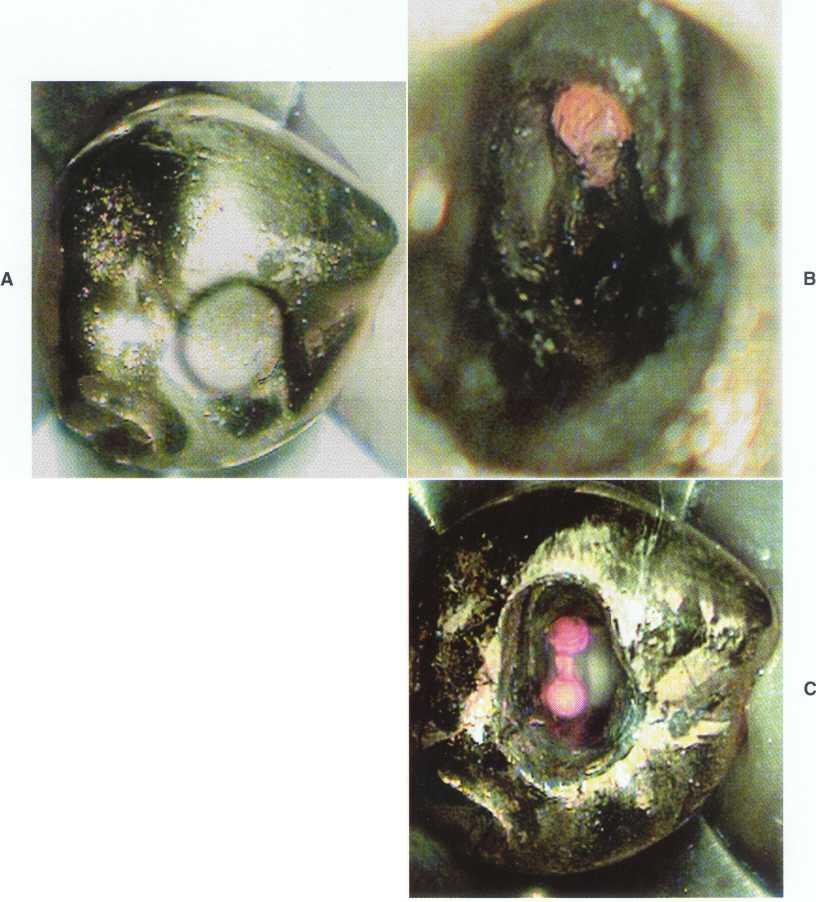

FIGURE 2-13 A, Removal of the amalgam permits inspection of the tooth for fractures. The use of microscopy allows identification of a mesiodistal fracture. The pulp chamber has not been entered. B, On entering the pulp chamber, the clinician notes a fracture across the pulpal floor from mesial to distal. Wedging a Glick instrument into the access allows the clinician to visualize the fracture spreading and closing in this hopeless tooth. Although this gross fracture was visible with loupes, the extent of many fractures cannot be seen. Diagnosis and prognostication then become guessing games at best. Note the white dot of the MB2 canal located (in vain) with a Mueller bur above the fracture about halfway between the fracture and the MB canal; this was not visible without the microscope.

VISION, MAGNIFICATION, AND ILLUMINATION

Although ultrasonic and Mueller bur techniques can be used without magnification, they are faster, more predictable, and safer with magnification. The operating microscope is the greatest teacher of endodontic anatomy4 (Figure 2-12). Previously difficult cases become stress

free with microscope use, and previously impossible cases become routine. With the enhanced vision and illumination of the microscope, the clinician operates in an entirely different mode-visually.

To become proficient with the microscope, the clinician should not pull it into service on only the most difficult cases. In fact, without the use of the microscope the clinician may not even be aware of factors increasing

FIGURE 2-14 A, The lingual view shows the incisally repositioned access with the rotary notch. B, From the lateral view, the darker wedge-shaped portion of the access shows how incisally this notch may be placed. With the repositioned access, very little cervical dentin needs to be removed.

the difficulty of the case and therefore miss cues only visible with the magnification and illumination the microscope provides (Figure 2-13).

Treatment of maxillary molars is never routine (Figure 2-22). In a recent study of maxillary first and second molars an MB2 canal was found in 96% of the mesiobuccal roots of maxillary first molars and 94% of the maxillary second molars. Approximately 54% were located in the traditional access opening, 31% were found with the use of a bur, and 10% were found with the aid of a microscope. The MBZ canal orifice was found on average 1.82 mm lingual to the main MB canal orifice.9 In another study of the maxillary first molar using microscopy, the MB Z canal was located in

93% of first molars and 60% of second molars4 (Figures 2-23 and 2-24). The difficulty in access, high percentage of fourth and even fifth canals, and root curvatures put even the "routine" maxillary molar in a high-risk category.3 Complicating factors such as limited opening, crowns, changes in tooth angulation, tooth position, and calcification make predictable treatment of these teeth challenging for even the most experienced clinician trained in microscopy, ultrasonics, and rotary instrumentation.